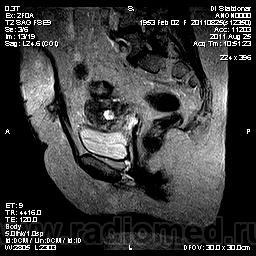

Пациентка поступила в клинику  с жалобами на подъём температуры, боли в левой подвздошной области. . Менопауза 6 лет.

В левой половине полости малого таза визуализируется мягкотканное объемное образование, исходящее из стенки кишки сигмовидного отдела кишечника, неправильной округлой формы, с четкими, бугристыми контурами, неоднородной структуры, за счет небольших жидкостных включений. Левая боковая стенка матки включена в структуру опухоли, отграничивающая полоска жировой ткани не прослеживается . Окружающая жировая клетчатка с признаками опухолевой инфильтрации. Левые подвздошные сосуды огибают наружный контур опухоли, интактны.

МР- картина с-r сигмовидной кишки с прорастанием левой боковой стенки матки и опухолевой инфильтрацией мезоректальной жировой клетчатки.